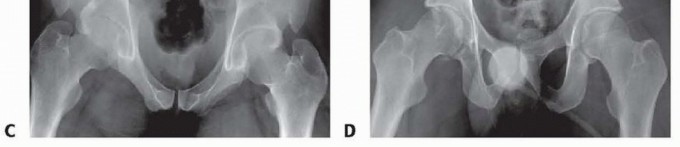

### FIG 2 • Examples of the anatomic variants between genders. The female pelvis has a more concave shape to the ring and the pubic arch has less of an acute angle because of the broader pubic body, as demonstrated in the inlet (A) and outlet (B) views of a female pelvis. The male pelvic ring is more oval, with a much more acute angle anteriorly because of the thinner pubic body, as seen the corresponding inlet (C) and outlet (D) views. Occasionally, lateral compression injuries involve fractures of the pubic rami and a symphyseal disruption. This occurs when the compressed hemipelvis causes the contralateral rami to fracture and the contralateral symphyseal body to tilt inferiorly. Because one side of the symphysis is off and can compress the bladder or uterus, altering the pelvic ring, it should be reduced to the other pubic body, which remains intact.

### FIG 5 • Appropriate AP (A), inlet (B), outlet (C), and Judet views (D,E) of the pelvis in a patient with pelvic trauma and wide pubic symphysis. (Courtesy of Jodi Siegel, MD, and David Templeman, MD.) 329 ## DIFFERENTIAL DIAGNOSIS Rami fractures Symphyseal strain Hip fracture Muscle strain or avulsion Lumbar fracture ## ACUTE MANAGEMENT The patients should be hemodynamically stabilized. The pelvis can be stabilized by placing ankles together with Ace wraps. Heels and ankles should be padded to prevent skin breakdown and ulcer formation. Placing a sheet across the pelvis at the level of the greater trochanters can be used to reduce the symphysis and temporarily stabilize the pelvis. The sheet can be affixed with towel clips to hold it with tension rather than tying a knot across the abdomen (see Cha 33). A pelvic binder can also be used in the same manner, but the authors prefer the sheet technique. ## NONOPERATIVE MANAGEMENT If minimal separation of the symphysis is present, the patient can be made non-weight bearing on the affected side and can be allowed to ambulate. Close radiographic monitoring should ensue, with weekly radiographs. Single-leg stance views can be used to help identify late instability. ## SURGICAL MANAGEMENT A diastasis larger than 2.5 mm indicates a disruption of the sacrospinous ligaments and thus an unstable pelvis. Open fixation of the symphysis stabilizes the anterior pelvis. 3 Open injuries can be stabilized with external fixation using iliac wing pins or Hanover pins placed at the level of the anterior inferior iliac spine. Refer to Chapter 33 for more details. Additionally, the technique of INFIX using pedicle screws at the anterior inferior iliac spine and a subcutaneously placed bar can also be used for obese patients. 17 In APC type II injuries with an intact hemipelvis, no posterior fixation is needed, and the symphysis is reduced and stabilized first. For type III injuries, if the innominate bone is broken, the anterior pelvic ring is reduced and fixed after the posterior ring is reduced and fixed. The anterior pelvic ring is reduced and fixed as a first step if the innominate bone remains intact. Indications for anterior stabilization for vertically unstable pelvic fractures include improving anterior stability to the pelvic ring, stabilizing a pelvic injury that is associated with an injury requiring a laparotomy, treatment of bone protruding into the perineum (ie, a tilt fracture), or in association with an acetabular fracture requiring open reduction. 13 ## Preoperative Planning The surgeon should review appropriate radiographic studies (AP, inlet, and outlet views and CT scan). Identifying all rami fractures and the presence of any pubic body fractures is essential, as this will help determine how to obtain a reduction as well as dictate the type of fixation necessary. The surgeon should plan to obtain stress views in the operating room to determine the stability of the pelvis if there is any question of stability. The surgeon should rule out the presence of a bladder rupture or urethral tear. If one is present, repair should be performed at the same time as internal fixation of the symphysis, if possible, to avoid a more complex late reconstruction. Any history of previous abdominal surgery or the presence of prior incisions should be identified before going to the operating room. The proper equipment must be available, such as C-arm, radiolucent table, large bone clamps, external fixation equipment, and a C-clam ## Positioning 330 The patient is placed on a radiolucent flat-top table with legs together to facilitate reduction of the symphysis. Fluoroscopic radiographs confirming the ability to obtain a good inlet and outlet views with the C-arm are obtained before preparing and draping the patient. Right-handed surgeons may prefer to have the C-arm on the patient's right side and the drill and instruments on the patient's left for easier access to the symphysis with the drill. Placement of a Foley catheter is needed to decompress the bladder; it can also be felt intraoperatively to help identify the bladder. Venodyne boots are placed on both legs if possible for deep vein thrombosis prophylaxis during the case. ## Approach Open reduction of the symphysis is performed with an anterior Pfannenstiel approach. ## TECHNIQUES